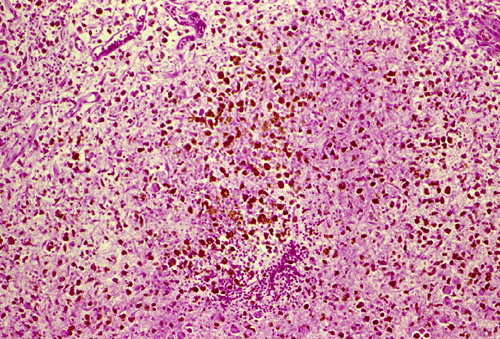

Histopathology: The hemorrhage, not surprisingly, is composed of blood (Panel B). At the periphery of the hemorrhage are areas that are heavily infiltrated by macrophages accompanied by substantial hemosiderin depositions (Panel C). On medium magnification, the blood vessel walls seems to be thickened and some ill-defined deposition are present in the wall (Arrow in Panel D). Immunohistochemistry for amyloid-b (Ab) was performed and the depositions in the vessel wall are positive.

Microscopically, the pathology of hemorrhage is not different from that of hemorrhage due to other causes. However, the blood vessels, particular the arterioles and the leptomeningeal vessels appear to have thickened wall and some clumpy irregular, eosinophilic depositions may be seen.   The depositions are also positive for periodic acid Schiff stain. The affected vessels in Ab caused CAA often have segmental dilatations, microaneurysm formation, and fibrinoid necrosis. The small muscle layer is often destroyed. In severely affected vessels, a double-barrel vessel wall is present.The amyloid depositions will stain bright orange-red with Congo red and will give a green birefrigence under polarized light.  In addition, immunohistochemical detection would be positive for Ab in many of the sporadic cases. P-component which almost always co-deposit with amyloid can also be detected by immunohistochemistry. At the ultrastructural level, Ab amyloid appears as clumps and bundles of straight filaments of 10 nm in diameter.